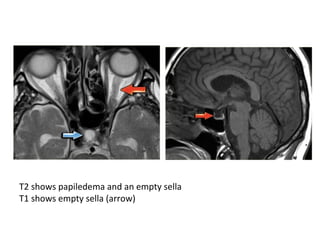

Attenuated vein sign in both ICVs (thin arrows), in the SS (crossed arrow)

CT+C shows contrast-filling defects in the ICVs (thin arrow) and the SS

(crossed arrows)